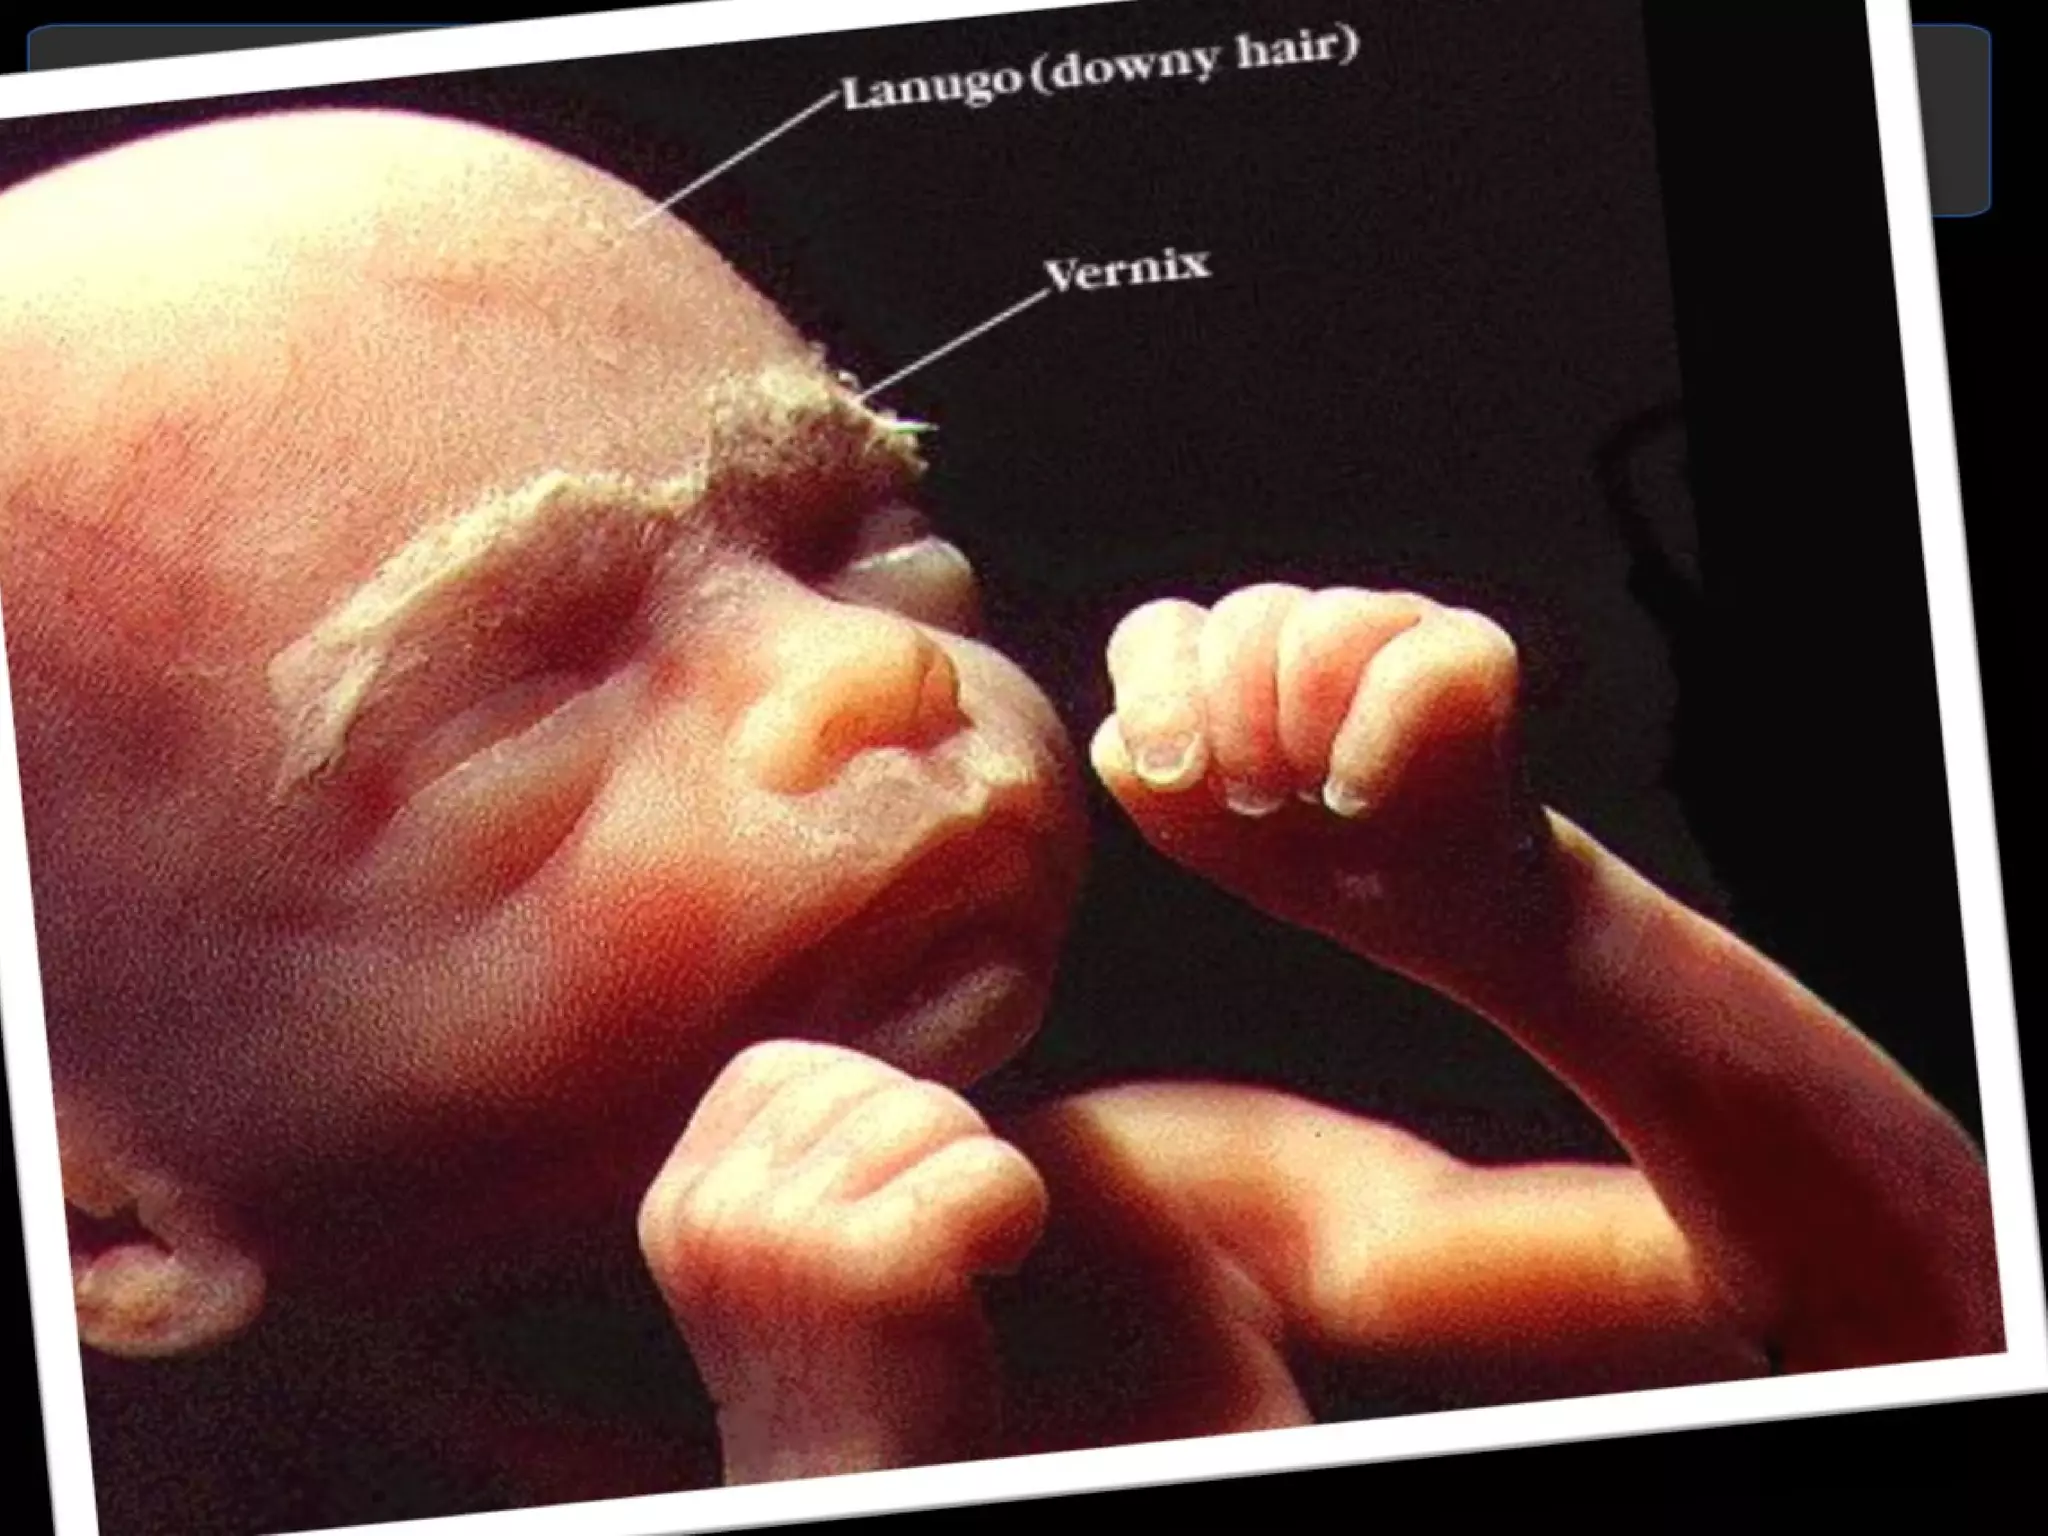

Respiratory System 7 th  week of IUL diaphragm completely divides the thoracic cavity from the abdominal cavity.  Between the 24 th  and 28 th  weeks alveoli and capillaries must be complete before gas exchange can occur in the fetal lungs  24 th  week of pregnancy alveolar cells begins to produce  surfactants  Surfactants has two components Lecithin and Sphingomyelin (2:1) INTEGUMENTARY SYSTEM The skin appears thin and translucent until subcutaneous fats begins to deposited at about 36 weeks. (lanugo, vernix caseosa)

Month 5  Second Trimester At the end of 5 months:   Baby is 8 to 10 inches long  Weight is about 1 pound  Hair begins to grow on baby's head  Soft woolly hair called lanugo will cover its body. Some may remain until a week after birth, when it is shed.  Mother begins to feel fetal movement  Internal organs are maturing  Eyebrows, eyelids and eyelashes appear

Month 6  Second Trimester At the end of 6 months:   Baby is 11 to 14 inches long  Weight is about 1 3/4 to 2 pounds  Eyelids begin to part and eyes open sometimes for short periods of time  Skin is covered with protective coating called vernix  Baby is able to hiccup

Respiratory System 7th week of IUL diaphragm completely divides the thoracic cavity from the abdominal cavity. Between the 24 th and 28 th weeks alveoli and capillaries must be complete before gas exchange can occur in the fetal lungs 24 th week of pregnancy alveolar cells begins to produce surfactants Surfactants has two components Lecithin and Sphingomyelin (2:1) INTEGUMENTARY SYSTEM The skin appears thin and translucent until subcutaneous fats begins to deposited at about 36 weeks. (lanugo, vernix caseosa)